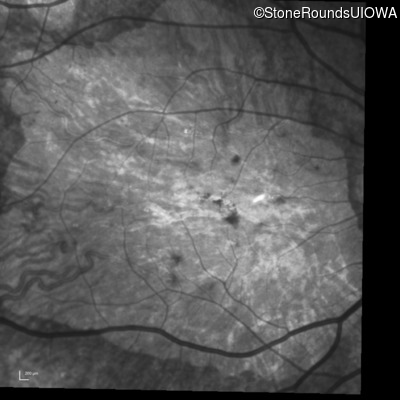

Infrared Fundus Photograph - Right - 20/250 sc

Exemplar